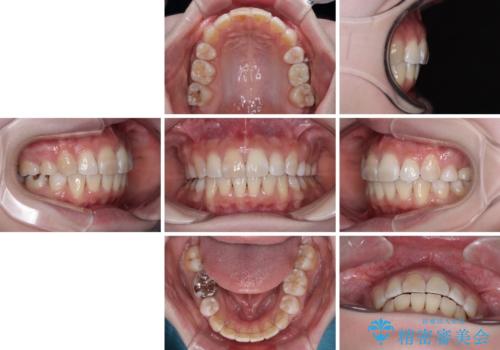

- 奥歯の欠損と、抜歯矯正の後戻りを気にして来院された患者様です。

上下前歯をワイヤー保定していましたが、強い舌の突出癖により上下ともにスペースができ、上下前歯は非接触になっていました。

また、上顎臼歯は虫歯により抜歯されてから放置されている状態でした。

舌の突出癖を改善したことで、突出感のあった口元の印象も、やや引っ込めることができました。